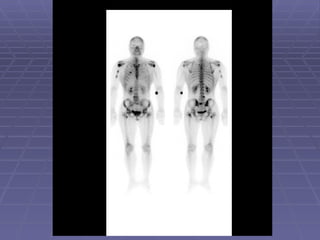

Acute Osteomyelitis   Early plain radiography signs of osteomyelitis are non-specific. 3-phase bone scan is usually the procedure of choice to differentiate between osteomyelitis and cellulitis.

Acute Osteomyelitis-cont.. If first and 2nd phases are positive (hyperemia) with normal third phase, diagnosis would be cellulitis. In acute osteomyelitis all 3-phases are positive (hyperemia and osteoblastic process in the bone).

Acute Osteomyelitis-cont.. Iffirst and 2nd phases are positive (hyperemia) with normal third phase, diagnosis would be cellulitis. In acute osteomyelitis all 3-phases are positive (hyperemia and osteoblastic process in the bone).